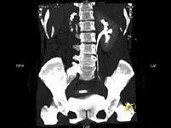

- 多项选择题女,35岁, 右侧腰部不适,CT增强扫描如图所示, 下列说法正确的是 ( )

A、右肾轮廓明显小于左侧,边缘光滑规则

B、左肾代偿性肥大

C、考虑为右小肾畸形

D、右肾完全无功能

E、考虑为右肾肾自截